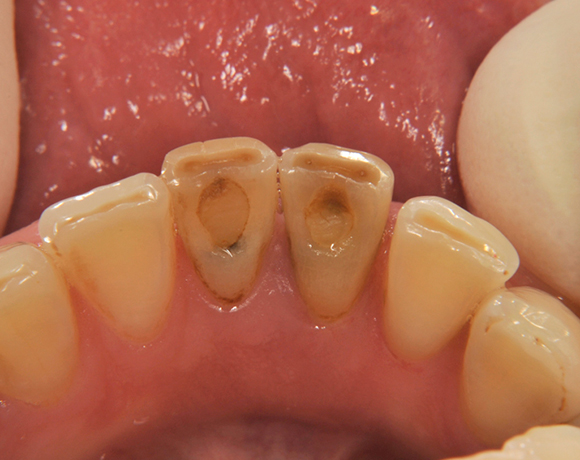

Im vorliegenden Patientenfall wurden die beiden nicht erhaltungswürdigen, mittleren Unterkieferschneidezähne durch zwei Vollkeramikimlpantate ersetzt.